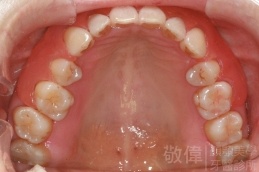

齒顏矯正/上顎暴牙且牙齒極度混亂

矯正前-上   矯正前-下

<個案說明>

上顎暴牙且牙齒極度混亂,經由矯正之後,臉型大幅度改善,牙齒的排列更加的整齊健康。相較於之前眼神充滿精神,自信心展現無遺。